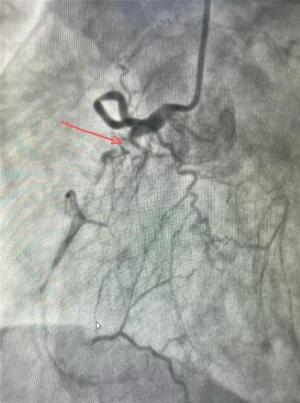

犍为县人民医院:分级诊疗见实效 优质医疗惠民生

近日,患者李女士将一面写有“医德高尚医术精 情系病患暖人心”的锦旗送至犍为县人民医院心血管内科,对副主任彭宇、管床医生谢加文的倾心服务表示高度认可和衷心感谢。患者李某某,一年前出现活动后心累、胸闷、双下肢水肿等情况,在当地医院治疗效果欠佳,病情反复。今年6月15日病情再次加重,到犍为县人民医院心血管内科治疗,经心电图、冠脉造影等检查,显示患者三支血管重度病变,且伴有长节段慢性完全性闭塞,由于患者病